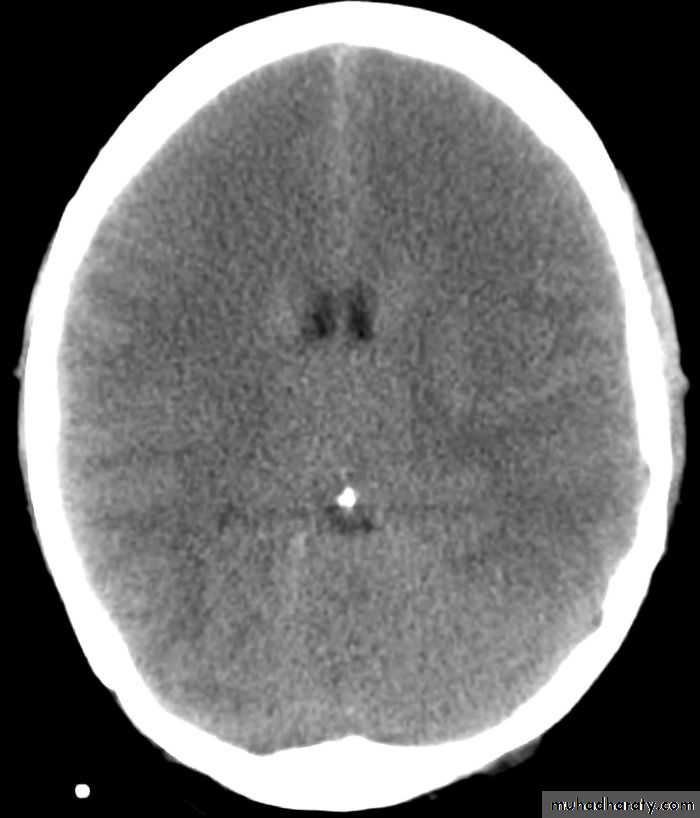

III- Brain edema:

Normal brain oedematous brain

Diagnosis:Clinically by deterioration of the general condition.

CT scan will show decrease in the size of the ventricles because when

there's edema it will press the brain and lead to decrease in the ventricles

size, also there will be decrease in the density of brain tissue (the color of the

brain tissue will be slightly lighter), but these findings are usually not

significant

Diagnosis is not easy because the ventricles are already small in size, so it is almost diagnosed by exclusion of hematoma or other causes.